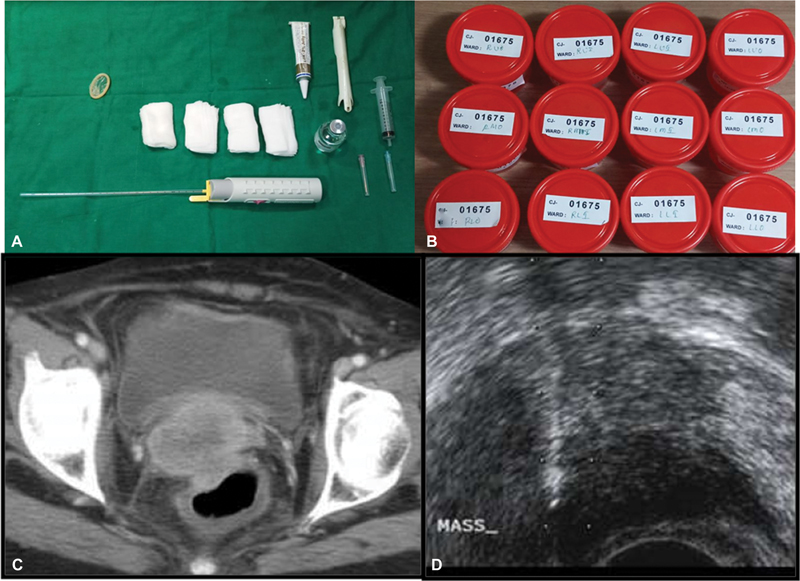

USG guidance-The needle can be inserted parallel or perpendicular to the transducer with the freehand or hand-guided technique. The tip needs to be visualized during needle insertion as an echogenic complex. Multiple punctures of the liver/renal capsule should be avoided to avoid the risk of bleeding. TRUS (trans-rectal)/TVUS (trans-vaginal) route can be used to biopsy prostate, vaginal/cervical vault lesions, and other deep-seated pelvic lesions ([Fig. 6]).[18]

| Figure 6:(A-B) Instrumentation used in TRUS guided biopsy and 12 containers for 12 core biopsy of the prostate. (C-D) Axial CT shows an ill-defined cervical mass sampled through TRUS guided approach.

| Figure 6:(A-B) Instrumentation used in TRUS guided biopsy and 12 containers for 12 core biopsy of the prostate. (C-D) Axial CT shows an ill-defined cervical mass sampled through TRUS guided approach.